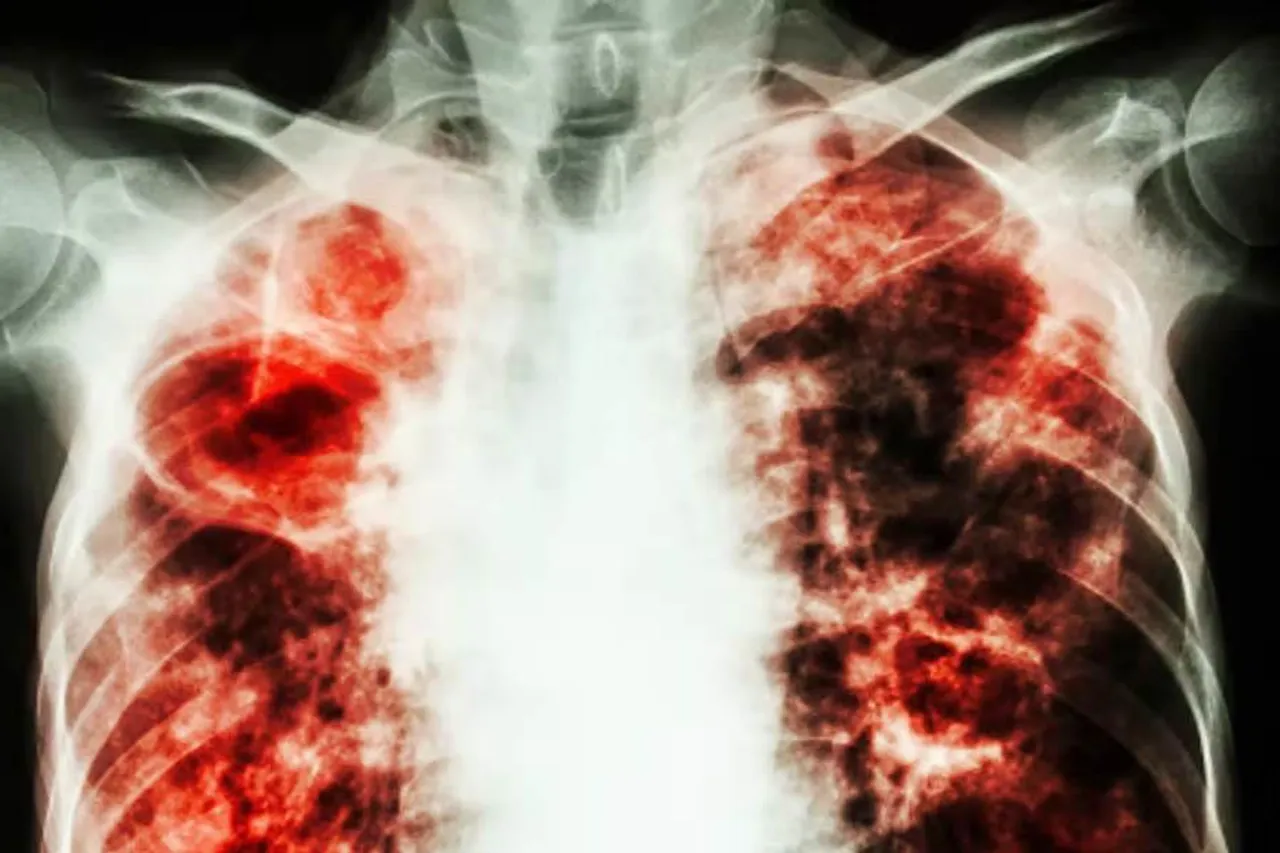

নিজস্ব সংবাদদাতাঃ আজ বিশ্ব যক্ষ্মা দিবস। আজকের দিনটিতেই ডাঃ রবার্ট কোচ টিবি সৃষ্টিকারী ব্যাকটেরিয়া আবিষ্কারের ঘোষণা করেছিলেন। ১৮৮২ সালে এই আবিষ্কারের স্মরণে, দিনটি বিশ্বব্যাপী পালিত হয়। ২০২২ সালে বিশ্ব যক্ষ্মা দিবসের থিম হল " যক্ষ্মা বন্ধ করতে বিনিয়োগ করুন। জীবন বাঁচাতে।" থিমটি এই রোগ নির্মূল করার জন্য প্রয়োজনীয় বিনিয়োগ এবং সংস্থানগুলির প্রয়োজনীয়তার উপর দৃষ্টি নিবদ্ধ করে। এই রোগের বিরুদ্ধে লড়াই করার জন্য তাদের কিছু উপায় অবলম্বন করা দরকার। থিমটি 'WHO' দ্বারা সার্বজনীন স্বাস্থ্য কভারেজ অর্জনের জন্য টিবি প্রতিরোধ ও যত্নের অ্যাক্সেস নিশ্চিত করে। যক্ষ্মার নির্দিষ্ট লক্ষণগুলির মাধ্যমে শনাক্তকরন করা যেতে পারে। যদিও লক্ষণগুলি সাধারণত সুপ্ত পর্যায়ে দৃশ্যমান হয় না। এই লক্ষণগুলির মধ্যে রয়েছে: ১) অবিরাম কাশি যা কমপক্ষে ৩ সপ্তাহ স্থায়ী পর্যন্ত হয় তা যক্ষ্মা রোগের প্রধান লক্ষণ। ২) কাশির সময় রক্তের সাথে কফ উৎপন্ন হওয়া আরেকটি প্রধান উপসর্গ। ৩) ঠান্ডা লাগা, জ্বর, ক্ষুধা হ্রাস এবং ওজন হ্রাস অন্যান্য লক্ষণ। ৪)রাতের ঘাম এবং বুকে ব্যথাও এই রোগের অংশ। ৫)টিবি পেটে ব্যথা, জয়েন্টে ব্যথা, খিঁচুনি এবং ক্রমাগত মাথাব্যথার কারণ হতে পারে।